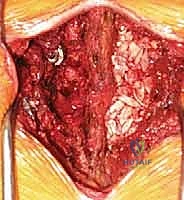

الخطوة 1: التجهيز والشق الجراحي

يتم وضع المريض على بطنه. يتم عمل شق جراحي دقيق في أسفل الظهر. باستخدام أجهزة الملاحة الجراحية والأشعة السينية الحية (Fluoroscopy)، يتم تحديد المستويات الفقرية المستهدفة بدقة.

الخطوة 2: إزالة الضغط العصبي (Decompression)

يقوم د. هطيف بإزالة الأجزاء العظمية الضاغطة (Laminectomy أو Facetectomy) والأربطة المتضخمة بدقة ميكروسكوبية لتحرير الأعصاب الشوكية المختنقة.